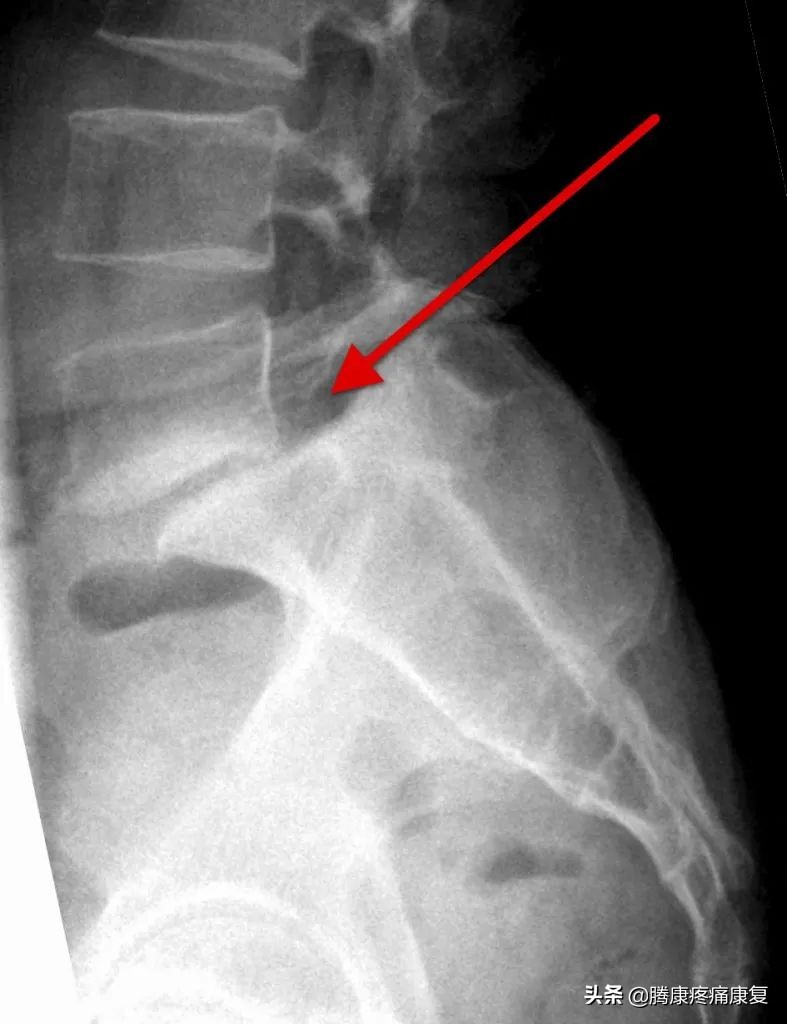

腰椎滑脱是一种比较常见的疾病,是指其中一节段椎体与下方椎体向前滑动或脱离。

脊椎滑脱有5种类型包括: 发育不良,峡部裂,退行性病变,创伤性病变和病理性病变 。其中退行性腰椎滑脱是最常见的类型,好发于20~50岁的成年人群,常见于L4~L5脊椎段,占总发病人群的60%以上。在退行性脊椎滑脱症中,椎体的前滑是由于正常老化过程中发生的脊柱退行性变化引起的。

这张图片显示了腰椎是如何随着时间的推移而退化的:

退行性椎体滑脱患者不会出现椎间隙骨折。这种腰椎峡部缺损常见于其他类型的脊椎滑脱,这有助于将这种类型与其他4种类型区分开来。

MRI/CT扫描可发现脊椎滑脱